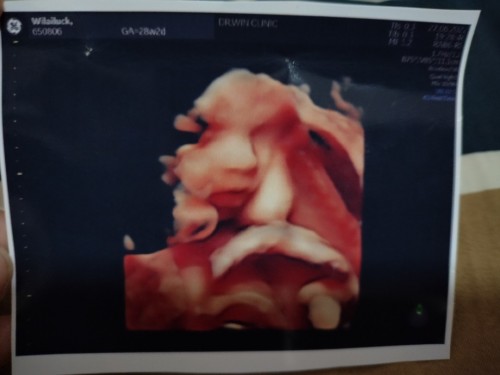

ถึงแม่หนูจะตัวเล็ก ท้องไม่ใหญ่ แต่น้ำหนักหนูตามเกณฑ์อยู่นะครับ👶🏻 28w4d 1095กรัม กำหนดคลอด17กันยายนครับ

จมูกโด่งเลยจ้า